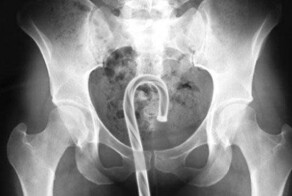

- Медик рассказала о любителях засовывать в себя разные предметы